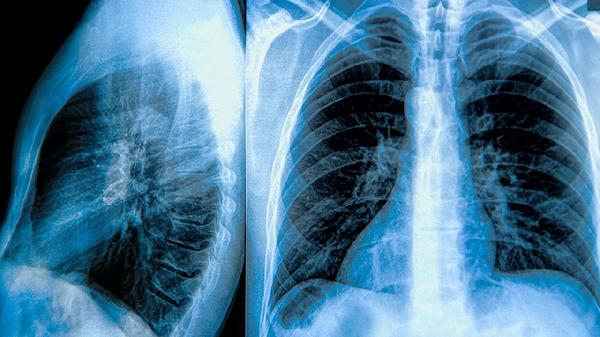

3、气胸的诊断:气胸的诊断主要依靠胸部X线检查,X线片上可见胸腔内气体影,肺部被压缩。CT检查可以更清晰地显示肺大泡的位置和大小,有助于确定治疗方案。